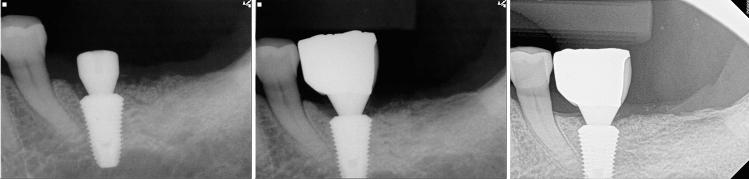

The purpose of the retrospective study was to investigate the long-term result of implant-induced injury on the adjacent tooth. The subjects of this retrospective study were patients who had received implants and had tooth injury; direct invasion of root (group I), root surface contact (group II), or < 1 mm distance of the implant from the root (group III). Clinical and pathological changes were periodically examined using radiographs and intra-oral examinations. Paired t-tests and chi-square tests were used to evaluate the implant stability quotient (ISQ) of implant and tooth complications, respectively (α = 0.05). A total of 32 implants and teeth in 28 patients were observed for average 122.7 (± 31.7, minimum 86) months. Seven teeth, three of which were subsequently extracted, needed root canal treatment. Finally, 90.6% of the injured teeth remained functional. Complications were significant and varied according to the group, with group I showing higher events than the others. The ISQs increased significantly. One implant in group I resulted in osseointegration failure. The implant survival rate was 96.9%. In conclusion, it was found even when a tooth is injured by an implant, immediate extraction is unnecessary, and the osseointegration of the invading implant is also predictable.

摘要

这项回顾性研究的目的是调查种植体对邻牙造成损伤的长期结果。该回顾性研究的对象是接受过种植体植入且存在牙齿损伤的患者;包括牙根直接受侵(I组)、牙根表面接触(II组)或种植体与牙根距离<1mm(III组)。通过X线片和口腔内检查定期观察临床和病理变化。分别采用配对t检验和卡方检验评估种植体的种植体稳定性商数(ISQ)和牙齿并发症(α=0.05)。共观察了28例患者的32颗种植体和牙齿,平均观察时间为122.7(±31.7,最短86)个月。7颗牙齿需要进行根管治疗,其中3颗随后被拔除。最后,90.6%的受伤牙齿仍保持功能。并发症明显且因组而异,I组的并发症发生率高于其他组。ISQ值显著增加。I组中有1颗种植体发生骨结合失败。种植体存活率为96.9%。总之,研究发现即使牙齿受到种植体损伤,也无需立即拔除,侵入性种植体的骨结合情况也是可预测的。